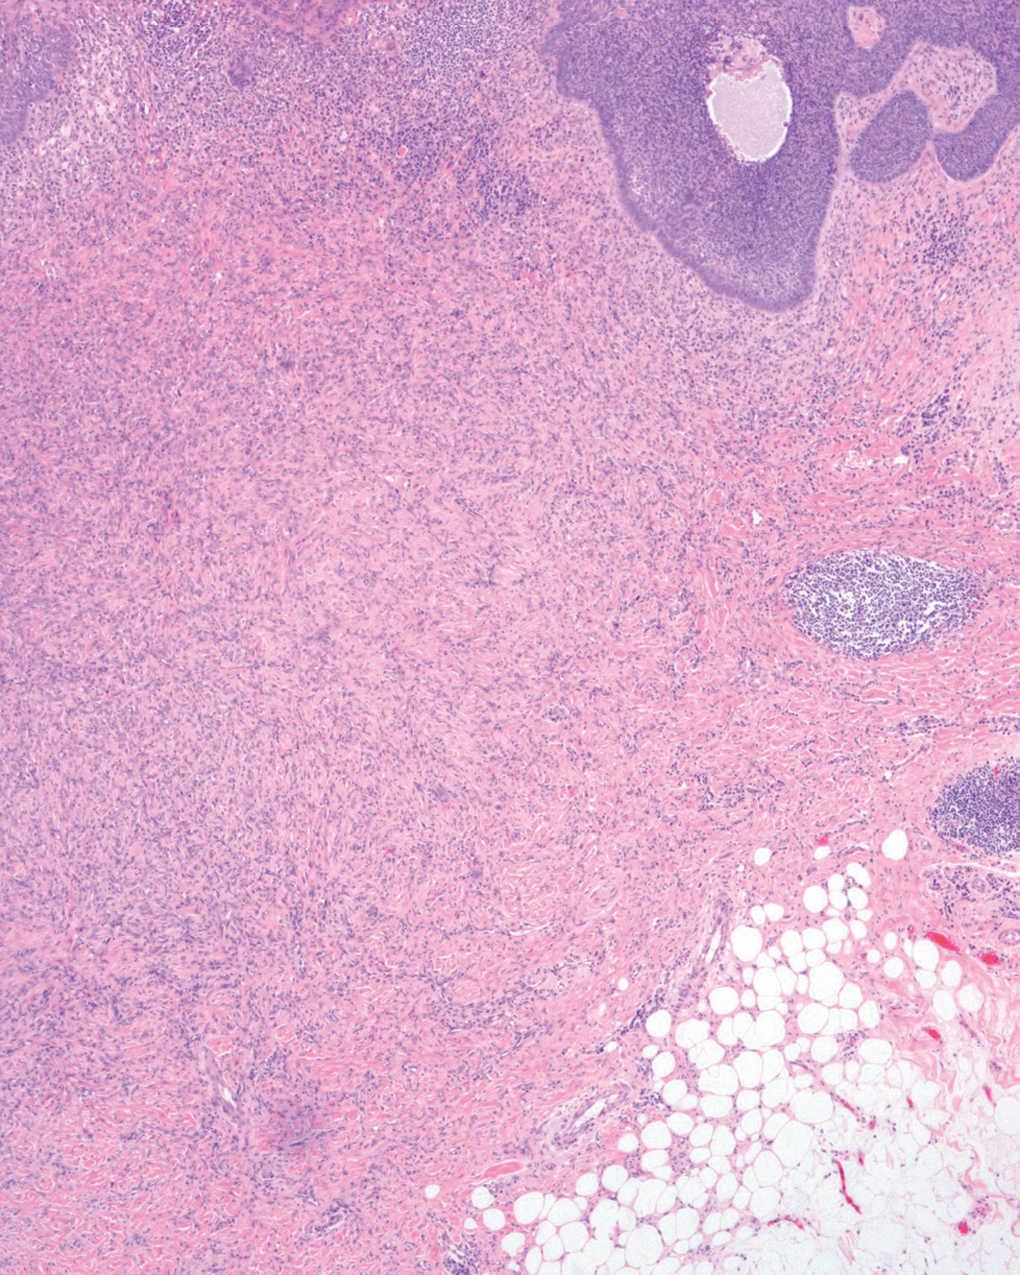

Se realizó extirpación completa de la lesión y se observó en el estudio anatomopatológico un nódulo dérmico localizado en dermis reticular, formado por una proliferación mesenquimatosa de células fusiformes sin atipias, con un patrón vagamente estoriforme. Entre ellas se apreciaban algunos histiocitos xantomizados, linfocitos y fibras de colágeno (fig. 1). Superficial a este nódulo se observó una proliferación epidérmica de células de hábito basaloide, que crecían en la dermis papilar formando pequeños nidos sólidos limitados por una capa de células en empalizada. Focalmente esta proliferación formaba nidos de mayor tamaño que infiltraban la dermis reticular. Algunos tenían degeneración quística central (fig. 2) y hendidura de separación con la dermis adyacente (fig. 3). Los cambios descritos en la epidermis eran idénticos a los observados en el carcinoma basocelular, y la proliferación fibrohistiocitaria presente en la dermis era diagnóstica de dermatofibroma.

Fig. 2.--Nidos sólidos limitados por una capa de células "en empalizada". Se aprecia degeneración quística central. (Hematoxilina-eosina, x20.)